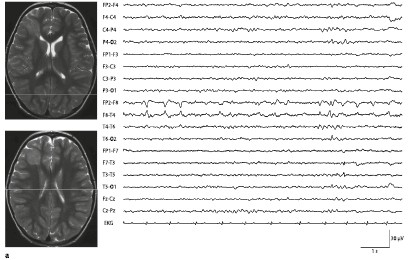

Abbildung 1 Hippokampussklerose Und Kortikale Dysplasie Typischer